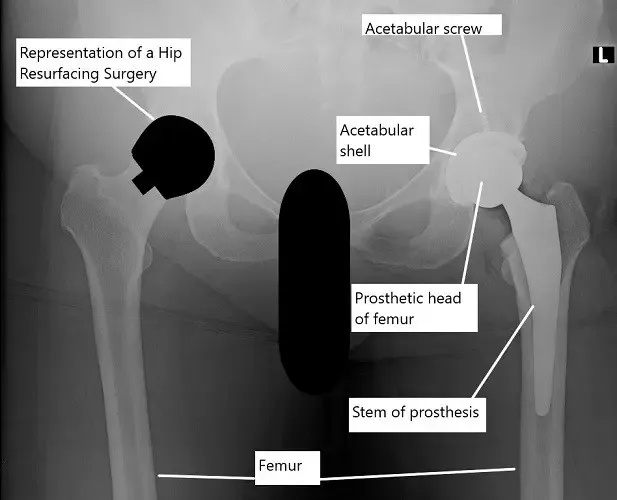

X-ray showing a total hip replacement on the left hip and an illustration of hip resurfacing on the right hip

Hip resurfacing surgery is a kind of hip replacement in which only the ball of the diseased hip is cut and replaced with a prosthetic implant. The socket is replaced in a similar fashion to a total hip replacement.